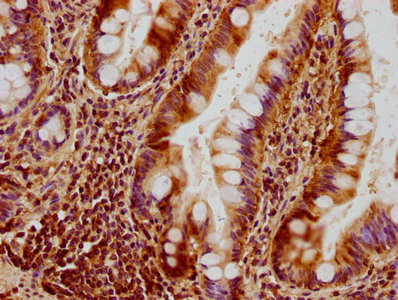

IHC image of CSB-PA016340HA01HU diluted at 1:300 and staining in paraffin-embedded human small intestine tissue performed on a Leica BondTM system. After dewaxing and hydration, antigen retrieval was mediated by high pressure in a citrate buffer (pH 6.0). Section was blocked with 10% normal goat serum 30min at RT. Then primary antibody (1% BSA) was incubated at 4°C overnight. The primary is detected by a biotinylated secondary antibody and visualized using an HRP conjugated SP system.